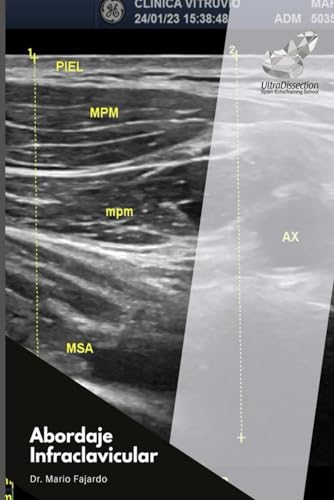

Abordaje Infraclavicular (Spanish Edition)